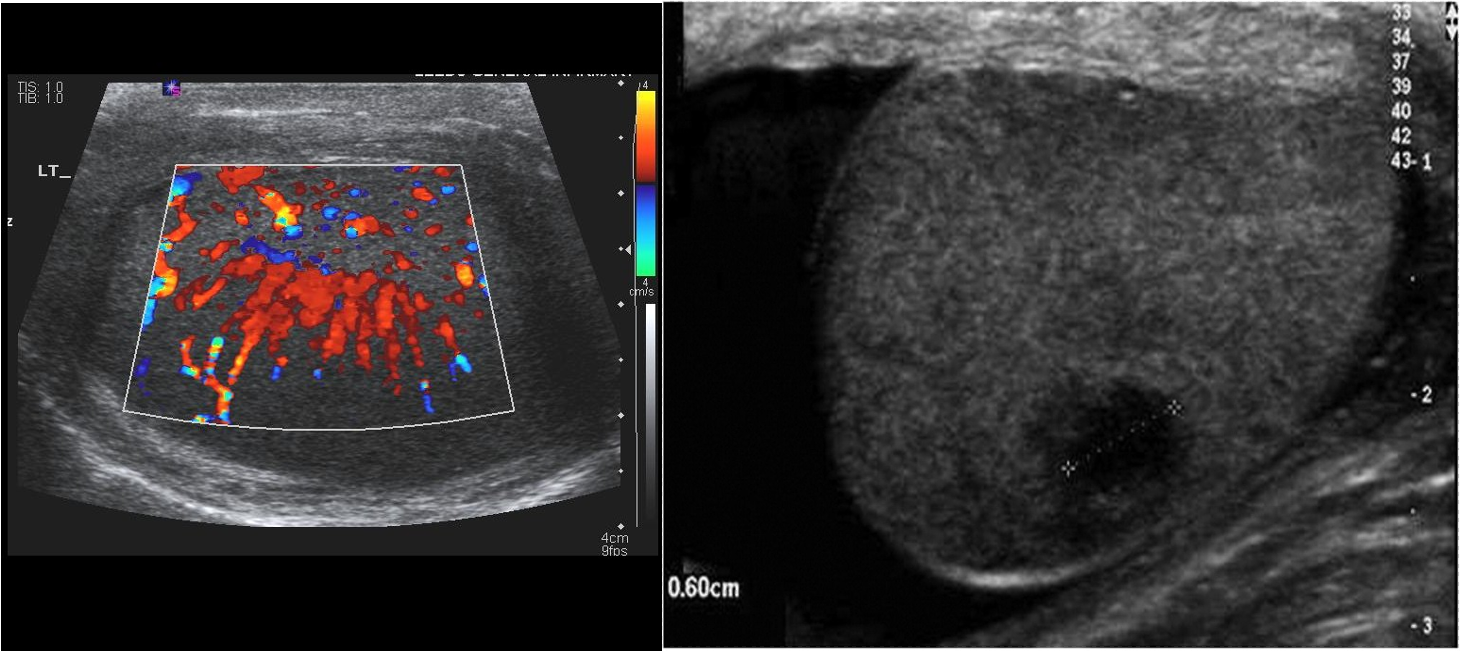

focal region of altered echogenicity and vascularity